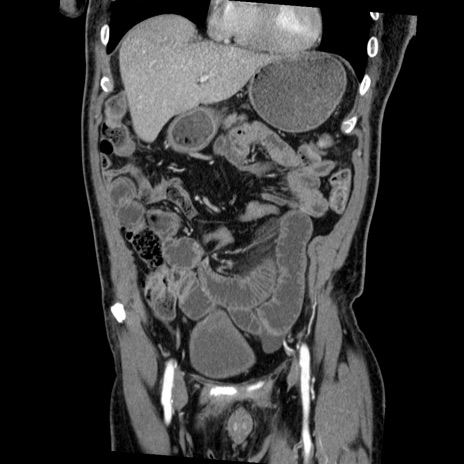

症例22(冠状断像)

【症例】50歳代男性

【主訴】腹痛

【現病歴】AVMからの被殻出血のため回復期リハ病棟入院中。 本日午後3時頃急に下腹部痛が出現した。

【既往歴】AVM、被殻出血、虫垂炎、高血圧

【身体所見】意識晴明、左半身不全麻痺、会話の理解は良好、36.5°C、腹部:膨隆、全体に板状硬、下腹部正中に圧痛点あり、反跳痛-、筋性防御不明、右下腹部にope scar

【データ】WBC 9400、CRP 0.06